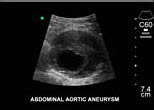

2.超音波檢查 B型超聲檢查可以了解下列問題:①有無腹主動脈瘤;②動脈瘤的大小;③動脈瘤腔內有無血栓形成,血栓的部位大小範圍及動脈瘤腔內通道口徑大小;④動脈瘤搏動的幅度。